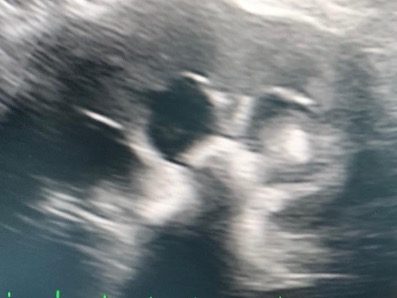

УЗИ мочевого пузыря (рис. 2), левой почки (рис. 3).